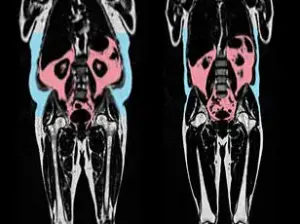

Researchers highlighted the importance of considering body composition, particularly the presence of visceral fat, which is linked to accelerated heart aging.

A separate study published in the European Heart Journal found that visceral fat—hidden deep within the abdomen around organs like the liver and intestines—can harm cardiovascular health even in individuals who appear slim.

This invisible fat, unlike subcutaneous fat, is associated with increased risks of heart disease and other metabolic disorders.

Body shape also emerged as a significant factor in heart health.

Men with an ‘apple-shaped’ body type, characterized by abdominal fat accumulation, were found to have more rapidly aging hearts compared to ‘pear-shaped’ women, who tend to store fat around their hips and thighs.

The latter group, known for gluteofemoral fat storage, exhibited healthier cardiovascular profiles.

These findings suggest that where fat is distributed on the body may be more predictive of heart health than total weight alone.